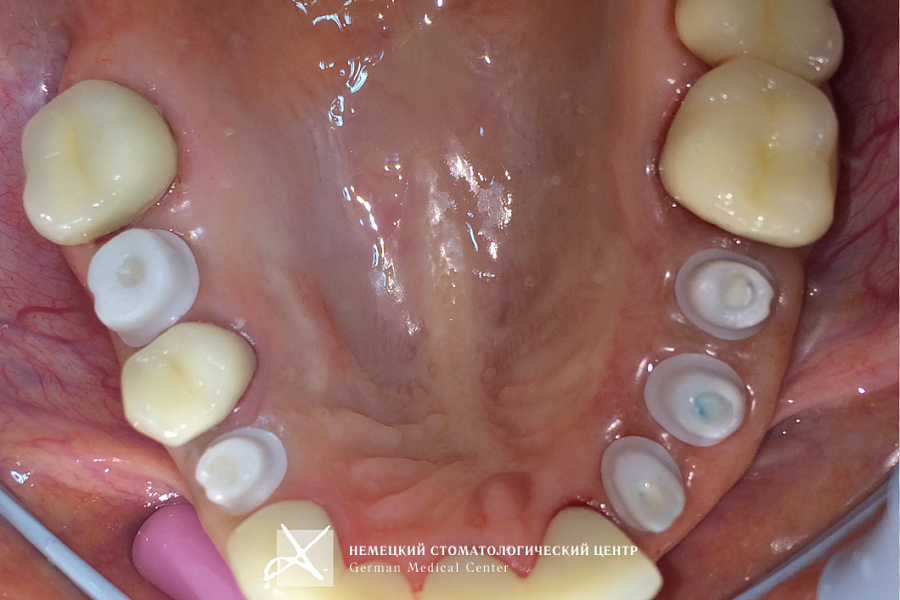

Пациентка обратилась с задачей восстановить целостность зубных рядов.

Пациентке проведено полноценное восстановление зубных рядов конструкциями с опорой на зубы и имплантаты. Коронки и абатменты изготовлены из диоксида циркония. Во время подготовительных мероприятий пациентка пользовалась временными конструкциями.